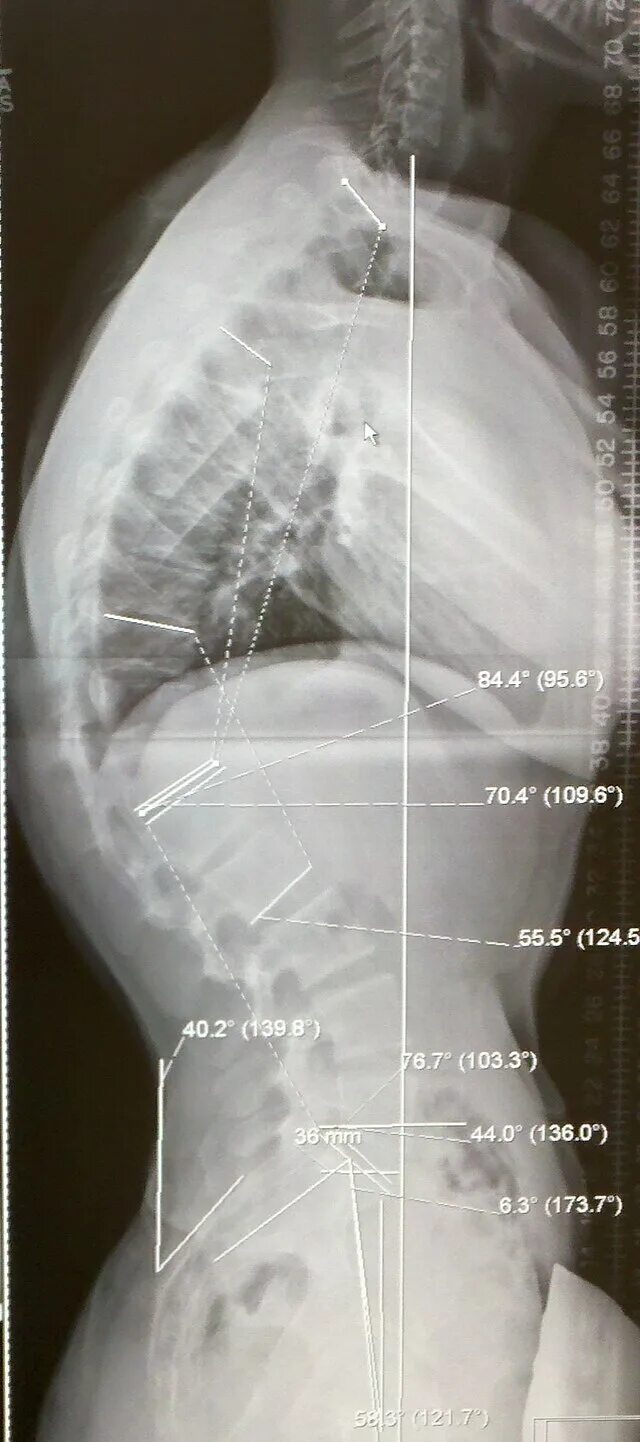

Болезнь шейермана мау код